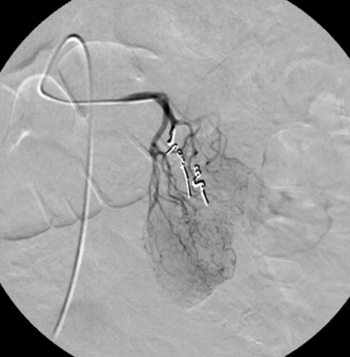

Digitale Subtraktionsangiografie: Superselektive Sondierung und Darstellung der mutliplen Blutungsherde. Die Leberarterien werden durch die zystischen Metastasen ausgespannt.

Digitale Subtraktionsangiografie: Nach Spiralembolisation mehrerer Subsegmentäste der A. hepatica stehen die zahlreichen Blutungen.